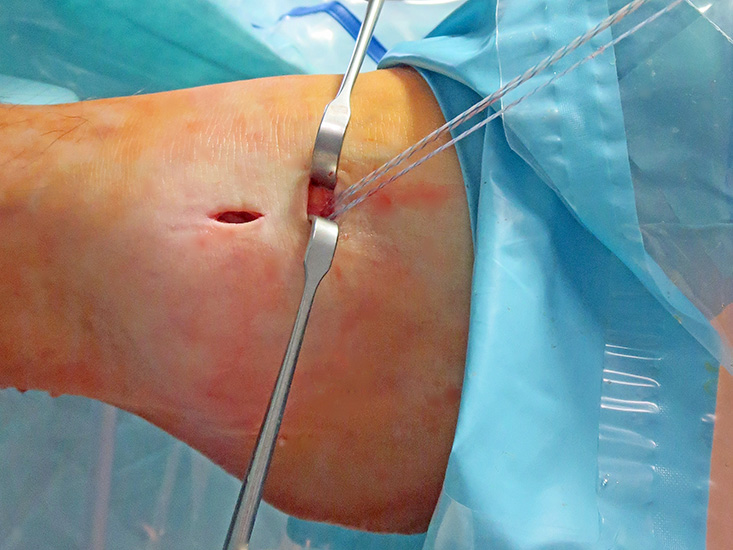

- Arthroskopisches Fadenholinstrument (Abbildung 1) oder eine gebogene kanülierte Ahle mit einer Drahtschlaufe (Abbildung 2).

Nachfolgend wird die OP-Technik an einem rechten Sprunggelenk unter Verwendung von PEEK-Ankern veranschaulicht.